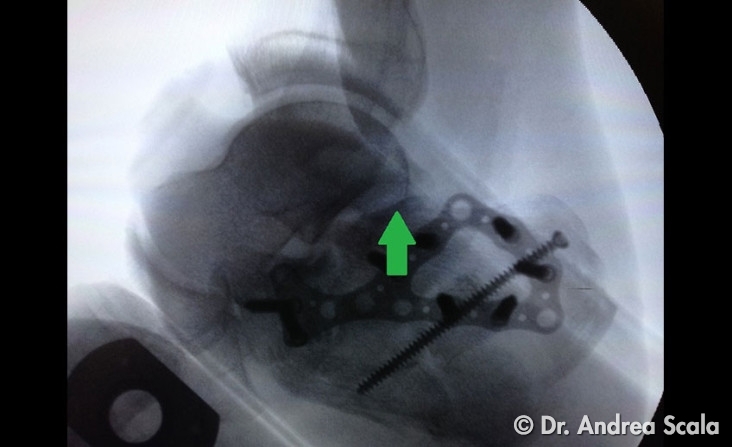

Alla fine dell’intervento il risultato della ricostruzione dell’articolazione del calcagno è stata soddisfacente. Le frecce verdi sulla radiografia post-operatoria fanno capire come è stata ricostruita l’articolazione, che era crollata al momento della frattura. La placca e le viti assicurano la stabilità della ricostruzione.